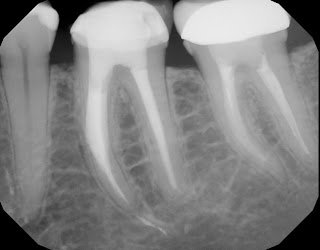

Removal of a separated instrument is rarely a simple task. The closer to the apex, the more difficult the removal. In this case, tooth #19 had a separated instrument 6 yrs earlier. The tooth had become symptomatic and the patient was having extensive crown and bridge work done.

A CBCT was taken to evaluate the separation in 3D. This image was very helpful because it told us the anatomy of the mesial root. It shows clearly that the mesial root is a single root, rather than two separate roots. With this information, we can plan to remove some tooth structure between the MB and ML canals in our attempt to access and remove the separated instrument. It also showed us that there were 2 separated instruments in the MB canal. This information is crucial in our ability to remove the spearated instrument. (The radiographic imaging also warned us not to remove any dentin mesial to the prepared space to prevent root perforation)